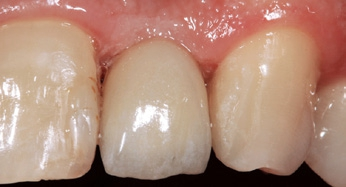

Der klinische Befund zeigte eine definitive Versorgung auf 12 und eine temporäre Versorgung auf 22. Dahingegen lag bei der Implantatversorgung in regio 22 der Verdacht auf eine partielle Fibro-Osseointegration vor (Abb. 1 und 2) [9,10].